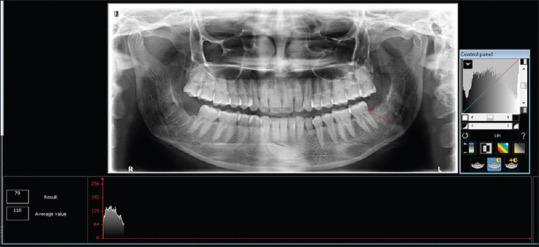

This split-mouth prospective trial constituted prophylactic removal of M3Ms with Sticky bone grafted in the study site as a primary predictor variable. Patients underwent 3 months of mandatory follow-up where pain, swelling, interincisal mouth opening, and gingival healing were measured on the 3, 7, and 14 day using the Numeric Rating Scale, anatomic landmarks, steel metric ruler, and criteria given by Landry . respectively. Radiological healing was calculated based on the height of the socket, Kelly's Index, and histogram values immediately after the procedure at 1 week, 1 month, and 3 months, respectively. Statistical comparison was made using Paired -test. < 0.05 was considered significant.

本双盲前瞻性试验将在研究部位植入粘性骨预防性拔除M3M作为主要预测变量。患者接受3个月的强制随访,分别在第3、7和14天使用数字评分量表、解剖标志、钢尺以及兰德里给出的标准测量疼痛、肿胀、切牙间开口度和牙龈愈合情况。分别在术后即刻、1周、1个月和3个月根据拔牙窝高度、凯利指数和直方图值计算放射学愈合情况。采用配对t检验进行统计学比较。P<0.05被认为具有显著性。